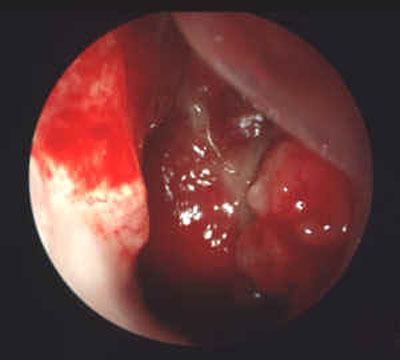

癌细胞转移形成头颈部癌 内窥镜观察肿瘤组织